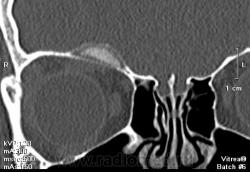

Девочка, 13 лет. К сожалению анамнеза толком не знаю, девочку не видела, снимали без меня. Основная жалоба на наличие "шишки". В направлении - исключить объемный процесс. Написала, что вероятнее всего фиброзная дисплазия. При несоответсвии клиническим данным рекомендуется биопсия. А сомнения остались. Как вы считаете что это может быть?

Вряд ли это псевдотумор. Мягкие ткани орбиты не изменены. Все в пределах кости. Кость вздута. Гемангиома - это вариант, на мой взгляд.

Шишка по верхнему краю орбиты.

Но, тут, ведь два патологических процесса - один в лобной пазухе, другой - в орбите?

Это "объём" в орбите?

Это нижний полюс "образования". Шишка похоже не связана с пазухой, а в орбиту вдается за счет вздутия кости. Завтра постараюсь выложить еще коронарных срезов.

Коронарные срезы.

Да я на первое место поставила фиброзную дисплазию. И порекомендовала биопсию при несоответствии клиническим данным. Надеюсь не ошиблась.

Жалко, что Вы девочку не видели, есть синдром Олбрайта, изменения идут не только костные, но и идет преждевременное половое созревание, так же наличие пегментных пятен. Возможно фиброзная дисплазия орбиты, только не приближена к классике.

Фиброзная дисплазия с обструкцией дренажа фронтального синуса. Интересное наблюдение. По синдрому Олбрайта - согласен с коллегой v1tal, ещё характерен невысокий рост (гипостатура).

Мой грех, девочку упустила. Спасибо, Марио, за ссылки. Правда очень похоже на фиброзную дисплазию.

Типичное место локализации метастаза нейробластомы у детей. Нужно обследовать брюшную полость и забрюшинное пространство